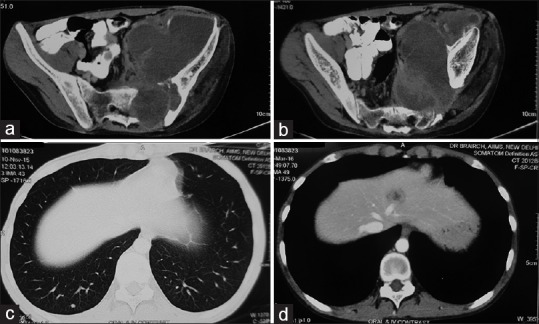

A 20-year-old male patient presented with a history of pain in the back, radiating down to his lower limbs for 2 years, urinary hesitancy for 1 year, and gradually increasing swelling in the left groin for 4 months. Neurological examination showed limping gait, wasting of the left lower limb muscles with an associated decrease in the power in left lower limb (left hip-grade 3/5, left knee flexors, and extensors-grade 3/5 and 0/5, respectively, left ankle-grade 2/5). Baseline magnetic resonance imaging of the pelvis, done 6 months before presentation at our institute, showed an expansile lesion of size 7.6 cm × 6.6 cm × 8.6 cm involving S2–S3 segment of sacral vertebrae with the involvement of the left sacroiliac joint and iliac bone with large intra-pelvic soft tissue component. The mass was obliterating adjacent sacral neural foramen and compressing intra-pelvic neurovascular bundle, left piriformis muscle, and sciatic nerve. The patient had been diagnosed at a local center with bone Tuberculosis and tubercular abscess and was started on anti-tubercular therapy (ATT), which led to symptom progression. Core biopsy from the sacral mass, performed at our institute, revealed a malignant tumor composed of pleomorphic cells and rhabdoid cells with abundant eosinophilic cytoplasm, vesicular nuclei, prominent nucleoli, intracytoplasmic juxta-nuclear eosinophilic inclusion, frequent mitoses, and large areas of necrosis. On immunohistochemistry, the tumor cells stained positive for cytokeratin, epithelial membrane antigen, vimentin, synaptophysin, MIC-2 (CD-99) and negative for smooth muscle actin, myogenin, glial fibrillary acidic protein, Bcl-2, CD-34, and Brachyury. There was a loss of expression of INI-1 in the nuclei of tumor cells. The morphological and immunohistochemical features of the tumor were consistent with a diagnosis of extrarenal rhabdoid tumor [Figure 1]. Bone marrow biopsy and whole body bone scan did not show any evidence of metastasis. A contrast-enhanced computed tomography (CECT) scan of chest, abdomen, and pelvis showed an increase in the size of the lesion (16 cm × 10 cm × 11 cm) with the tumor infiltrating the left psoas muscle, destroying the left side of sacrum, extending extradurally through the S1–S2 sacral foramen and also into the left gluteal and inguinal regions [Figure [Figure2a2a and andb].b]. There was a suspicious nodule in the lower lobe of the right lung suggestive of metastasis [Figure 2c]. Both kidneys were normal. CECT of the brain was essentially normal.

| Figure 2:(a and b) Computed tomography scan of pelvis with oral and intravenous contrast showing a lesion arising from the left side of sacrum with involvement of left sacro-iliac joint and left iliac bone, extradural extension through S1–S2 sacral foramina, intrapelvic soft tissue extension, infiltration of the left psoas muscle, and extension into the left groin; (c) computed tomography scan of thorax-lung window showing a suspicious nodule in lower lobe of right lung suggestive of metastasis; (d) contrast-enhanced computed tomography scan of abdomen showing an ill-defined lesion in segment 4a of liver suggestive of metastasis

In view of unresectable tumor and lung metastasis, he received 6 cycles of combination chemotherapy with ICE regimen (injection ifosfamide – 2 g/m2 intravenous [IV] D1–D3 with mesna uroprotection, injection carboplatin – 500 mg/m2 IV D3 and injection etoposide – 100 mg/m2 IV D1–D3), repeated every 3 weeks. Interim CECT scan of chest, abdomen and pelvis, done after 3 cycles of chemotherapy showed a 40%-decrease in the size of mass with resolution of the gluteal component suggestive of partial response. End-of-chemotherapy CECT scan of chest, abdomen, and pelvis showed a further 20%- decrease in the size of the primary lesion with the appearance of a new lesion in segment 4a of liver suggestive of liver metastasis [Figure 2d]. The patient was considered as unsuitable for curative surgery and palliative radiotherapy to the left hemipelvis to a dose of 20 Gray in 5 fractions over 1 week was planned by anterior and posterior fields with 6 MV X-rays on a medical linear accelerator (Varian CL 2300 C/D). The patient received 16 Gray in 4 fractions and then defaulted due to personal reasons. There was 50% subjective improvement 1 month after completion of radiotherapy in the form of improvement of muscle strength in the left lower limb (power-grade 4/5) and decrease in difficulty in walking. Subsequently, he was started on metronomic chemotherapy with a 4 drug combination of tablet celecoxib (200 mg BD), Tab thalidomide (100 mg HS) and alternating courses of tablet cyclophosphamide (50 mg OD) and tablet etoposide (50 mg OD) for 3 weeks each. Three months after the completion of palliative radiotherapy, there was good symptom control and CECT scan of the chest, abdomen and pelvis showed a further decrease (<20>